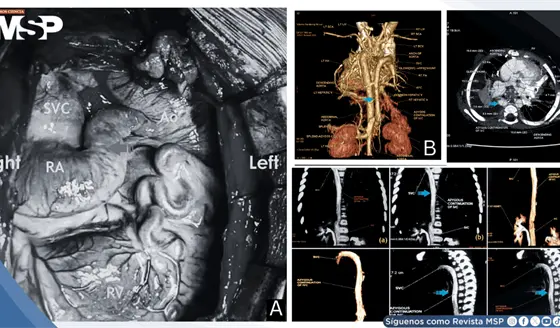

Desaturación sistémica temprana tras operación de Kawashima revela malformaciones veno-venosas